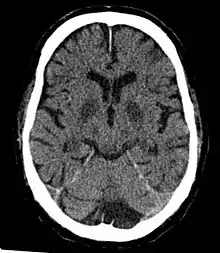

| Cerebral hypoxia | |

Cerebral hypoxia is a form of hypoxia (reduced supply of oxygen), specifically involving the brain; when the brain is completely deprived of oxygen, it is called cerebral anoxia. There are four categories of cerebral hypoxia; they are, in order of increasing severity: diffuse cerebral hypoxia (DCH), focal cerebral ischemia, cerebral infarction, and global cerebral ischemia. Prolonged hypoxia induces neuronal cell death via apoptosis, resulting in a hypoxic brain injury.[1][2]